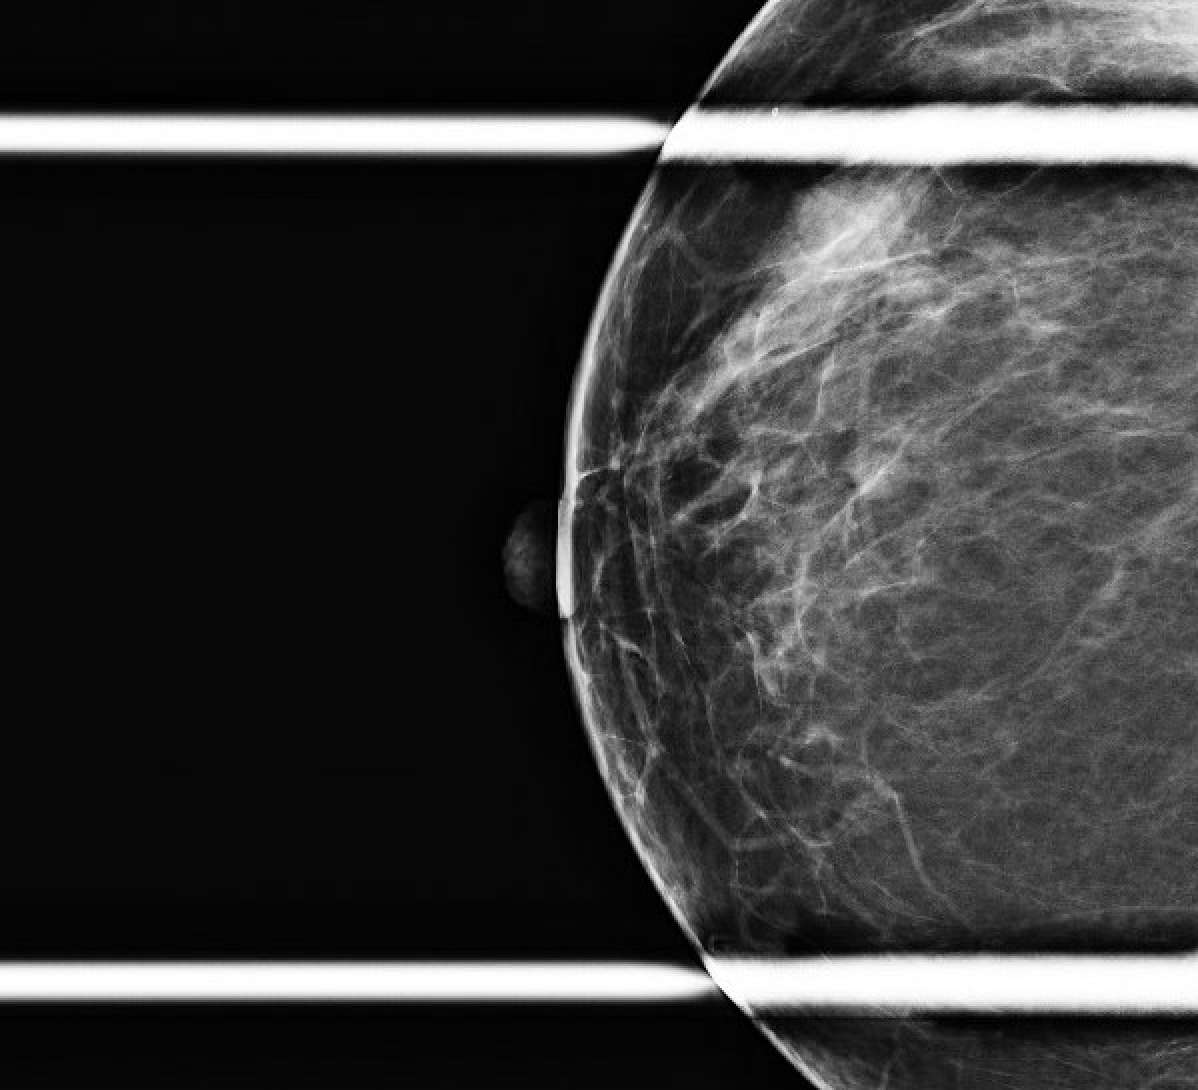

Se trata de una mujer premenopáusica de 46 años, sin antecedentes médicos o quirúrgicos, que acudió inicialmente a la clínica de cirugía mamaria después de que su mamografía anual de cribado descubriera una masa mamaria derecha no palpable de 0,6 x 0,8 x 0,7 cm a las 11 horas (oc), a 1 cm del pezón (FTN) (Figura 1). Se sometió a tres mamografías de detección previas sin ningún hallazgo notable. La mamografía de tamizaje se declaró no concluyente (BI-RADS 0) y se completó una ecografía mamaria con hallazgos similares. Una conversación más detallada con la paciente reveló que se había observado una secreción sanguinolenta en el lado derecho de su sostén en los últimos meses, pero no había otras preocupaciones o síntomas. Ante los hallazgos imagenológicos no concluyentes, se decidió realizar una mamografía diagnóstica para una valoración más específica (Figuras 2a y 2b) tras una biopsia con aguja gruesa guiada por ecografía y la colocación de un clip de localización para el diagnóstico tisular (Figura 3). La anatomía patológica reveló un papiloma intraductal con hiperplasia ductal y una metaplasia apocrina sin atipia. Dada su continua secreción sanguinolenta del pezón, hubo preocupación por posibles células premalignas subyacentes (discutidas más adelante); Por lo tanto, se recomendó que la paciente se sometiera a una mastectomía parcial. La masa permanecía inpalpable; por lo tanto, se colocaría un Savi Scout justo antes de la intervención operativa para ayudar a localizar el área de interés.

Figura 2a. Mamografía diagnóstica posterior a la biopsia. Vista oblicua mediolateral derecha, que incluye un área ampliada para un mejor detalle de la pinza de biopsia en espiral en el área de interés (flecha).

Figura 2b. Vista craneocaudal de la mamografía diagnóstica posterior a la biopsia. Incluyendo una imagen más cercana del área con el clip de biopsia en espiral (flecha).